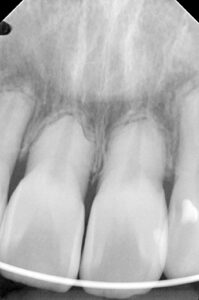

歯根吸収している患者さんです。

この方体質的に抗炎症剤を飲めない方でロキソニンを処方出来ないため歯根吸収が進行してしまった方です。

2025年7月

2025年12月

歯根の周囲の骨の白い部分が少なくなったのは炎症が少なくなった証拠です。

グルテンフリーは歯根吸収の原因の骨の炎症にも関係するのが分かります。